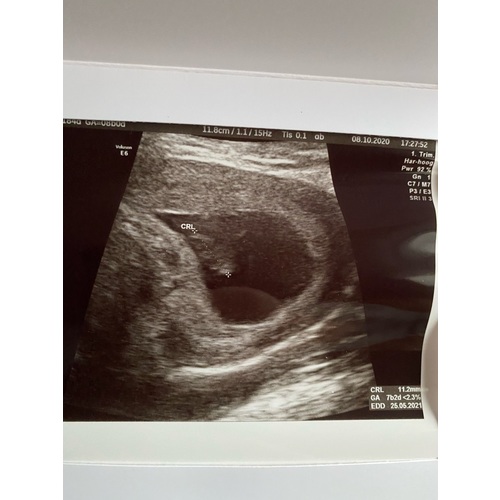

7w 2d! Uitwendig en hartje kunnen zien😊

Ik dacht 7w3d te zijn gisteren. Uiteindelijk gemeten op 7w6d en hartje klopte duidelijk 🥰

Mijn echo is ook van gisteren ben 7+4 daar. Hartje kon je duidelijk zien flikkeren.